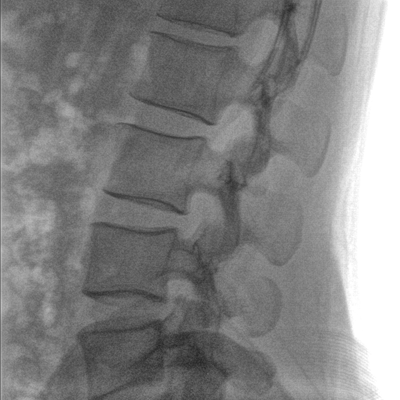

大尺寸液晶顯示器,圖像顯示清晰細(xì)膩;顯示器可大角度旋轉(zhuǎn),滿足臨床多角度觀察圖像的需要。

在球管和平板探測器兩端,分別加裝了激光定位系統(tǒng),滿足不同擺位無射線下的定位需求,降低醫(yī)患輻射劑量的同時,提高臨床工作效率。

具備束光器預(yù)覽功能,可以在無射線狀態(tài)下,實現(xiàn)曝光范圍大小的調(diào)節(jié);大幅減少臨床反復(fù)曝光帶來的射線輻射;并自動調(diào)整圖像興趣區(qū)大小與位置,使自動模式更準(zhǔn)確。